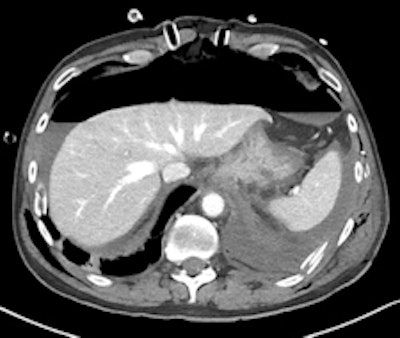

Gastroduodenal artery pseudoaneurysm in a 45-year-old man with pancreatitis and upper gastrointestinal bleed. Image courtesy of Dr. Paresh K. Desai and radiopaedia.org. radiopaedia.org/cases/gastroduodenal-artery-pseudoaneurysm.